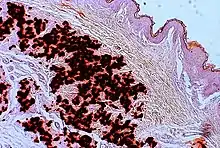

In PXE, there is mineralization (accumulation of calcium and other minerals) and fragmentation of the elastin-containing fibers in connective tissue, but primarily in the midlaminar layer of the dermis, Bruch's membrane and the midsized arteries.[26] Recent studies have confirmed that PXE is a metabolic disease, and that its features arise because metabolites of vitamin K cannot reach peripheral tissues.[27] Low levels of PPi cause mineralization in peripheral tissues.[19]

The diagnostic criteria for PXE are the typical skin biopsy appearance and the presence of angioid streaks in the retina. Criteria were established by consensus of clinicians and researchers at the 2010 biennial research meeting of the PXE Research Consortium.[29] and confirmed at the 2014 meeting[30] These consensus criteria state that definitive PXE is characterized by two pathogenic mutations in the ABCC6 or ocular findings – angioid streaks > 1 DD or peau d’orange in an individual <20 years of age together with skin findings:

- Diagnostic histopathological changes in lesional skin: Calcified elastic fibers in the mid and lower dermis, confirmed by positive calcium stain

| Pseudoxanthoma elasticum | LM: Mid-dermal calcification and fragmentation of elastic fibers EM: Mineralization in elastic fiber core |